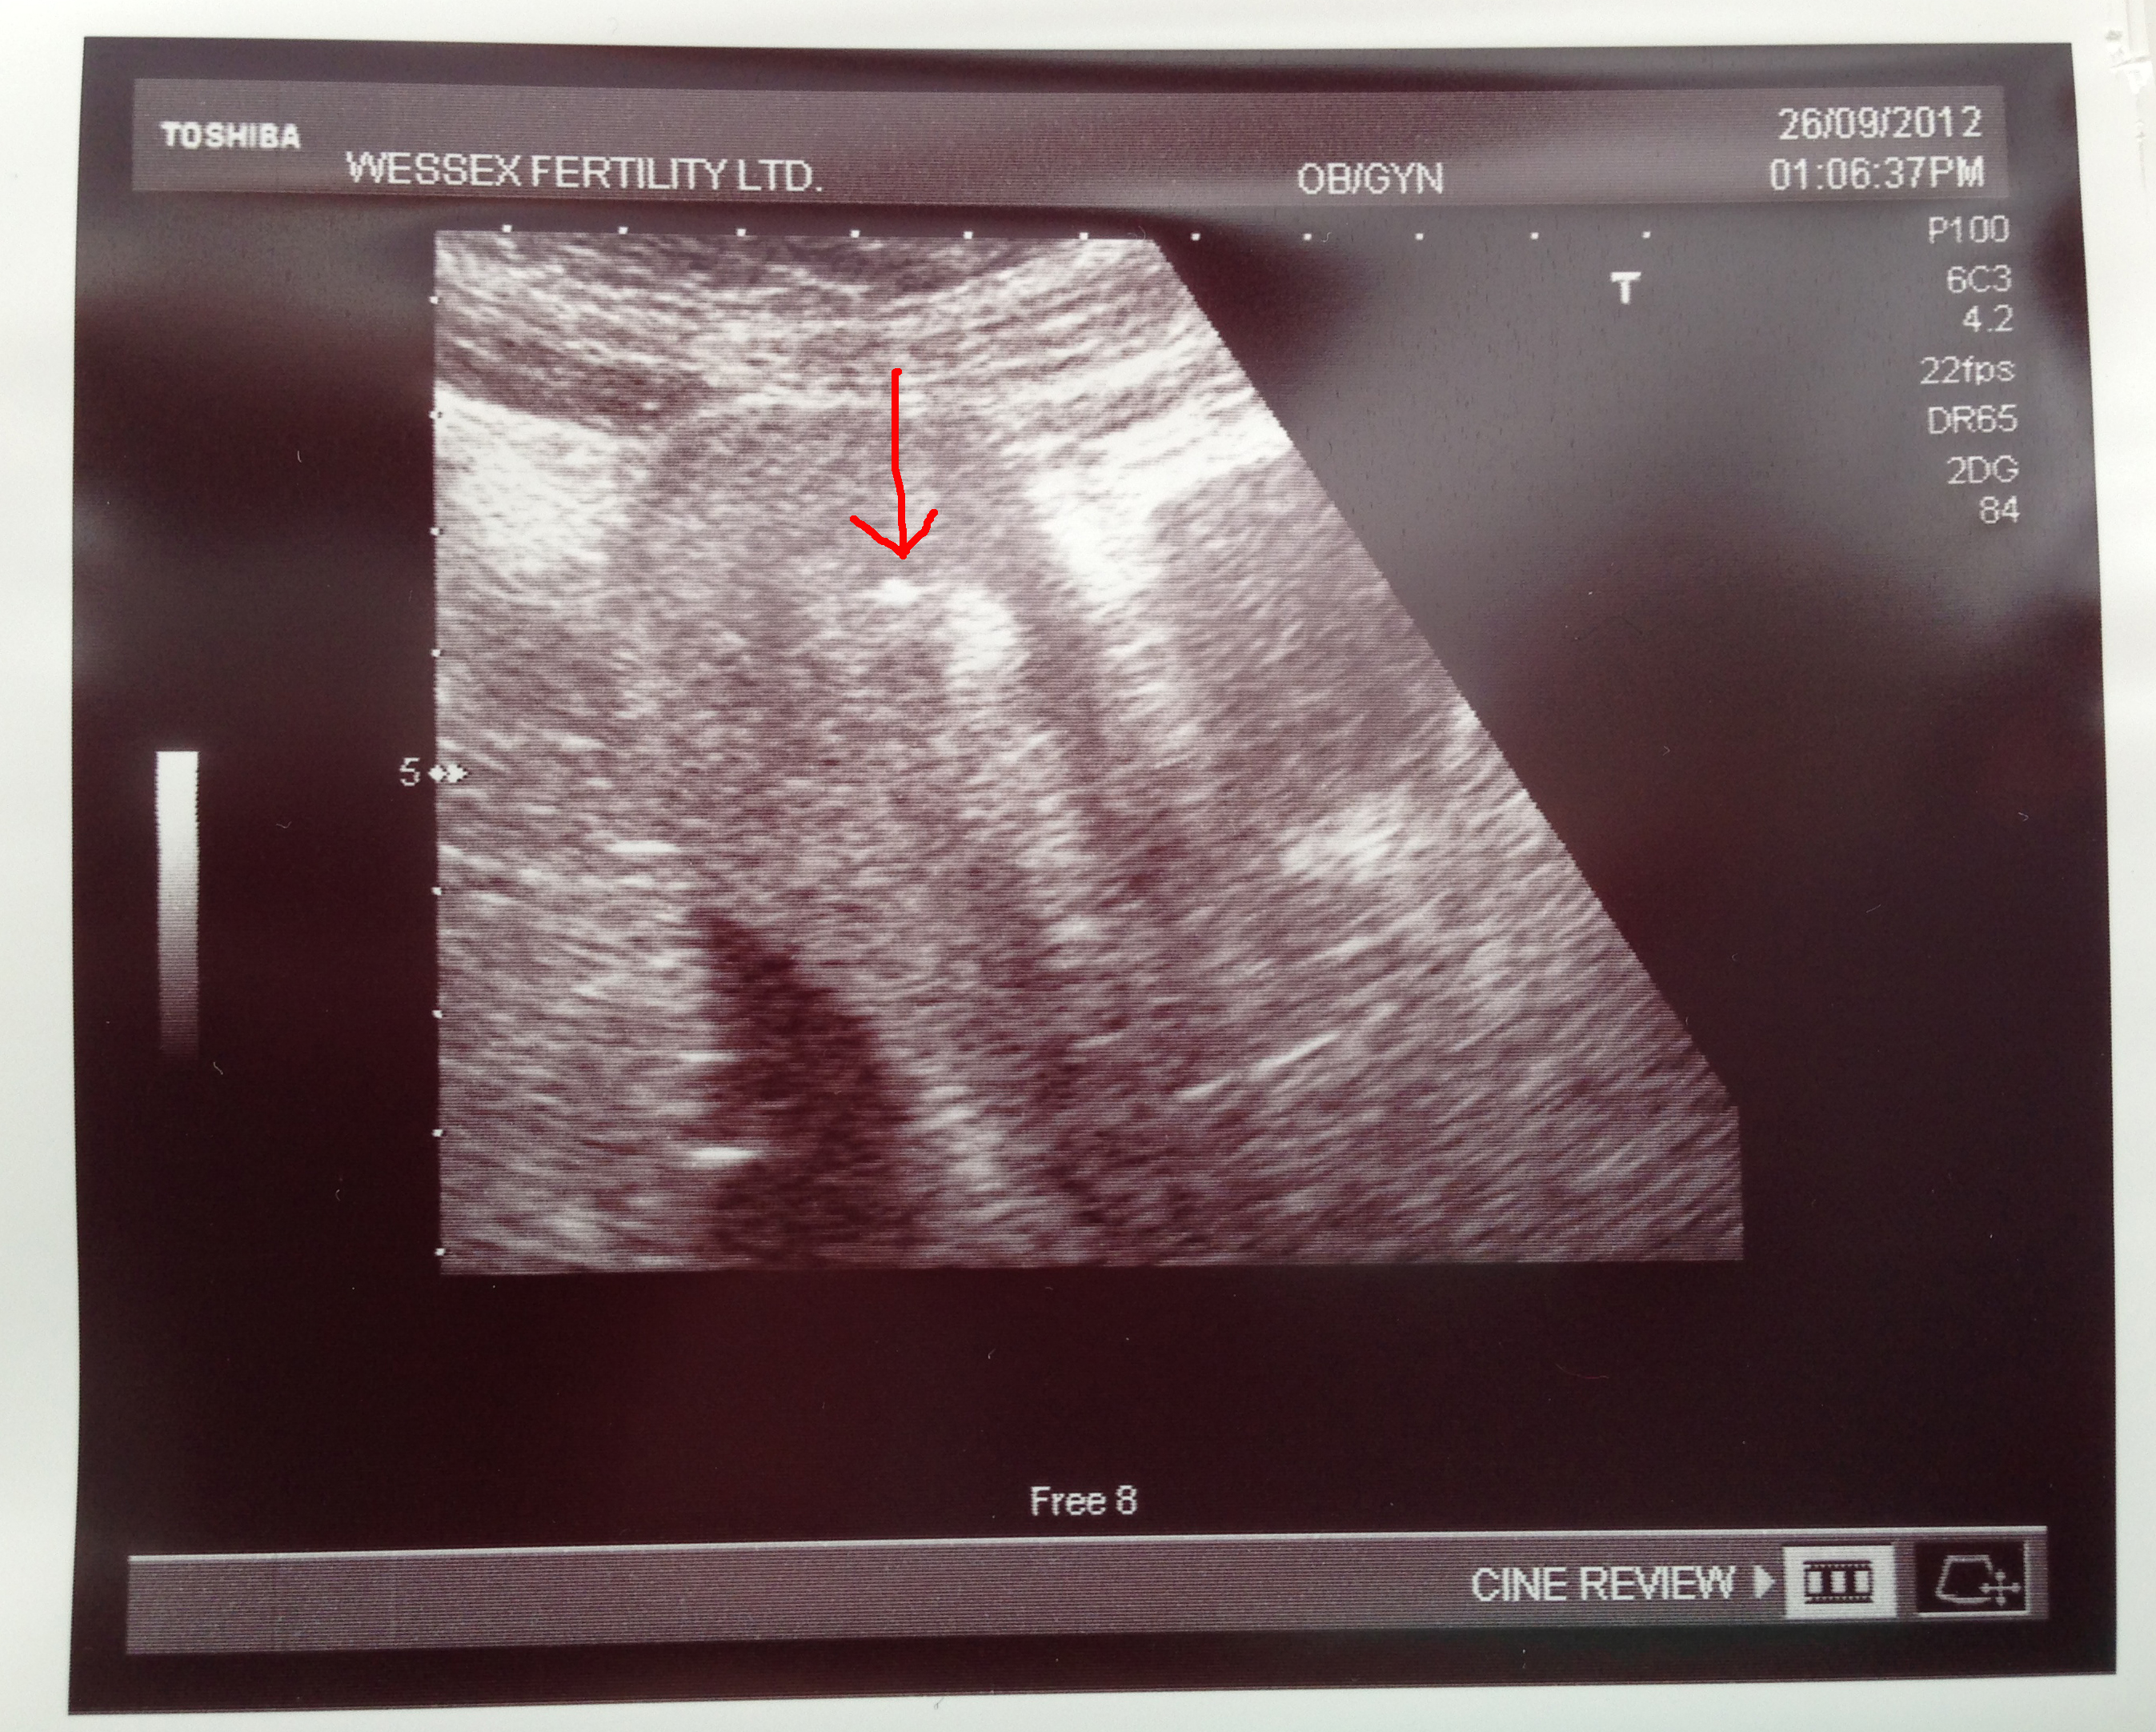

Then they inserted a fine tube through the cervix with the help of ultrasound. The embryos were passed down the tube into the womb and Jon could see all of this via the monitor! Lucky him.

Oh, below, a souvenir from the Clinic 🙂 The arrow points at a white blob, which is the two transferred embryos!